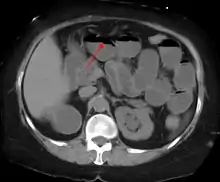

The main diagnostic tools are blood tests, X-rays of the abdomen, CT scanning, and ultrasound. If a mass is identified, biopsy may determine the nature of the mass.

Radiological signs of bowel obstruction include bowel distension and the presence of multiple (more than six) gas-fluid levels on supine and erect abdominal radiographs. Ultrasounds may be as useful as CT scanning to make the diagnosis.[17]

Contrast enema or small bowel series or CT scan can be used to define the level of obstruction, whether the obstruction is partial or complete, and to help define the cause of the obstruction. The appearance of water-soluble contrast in the cecum on an abdominal radiograph within 24 hours of it being given by mouth predicts resolution of an adhesive small bowel obstruction with sensitivity of 97% and specificity of 96%.[18]